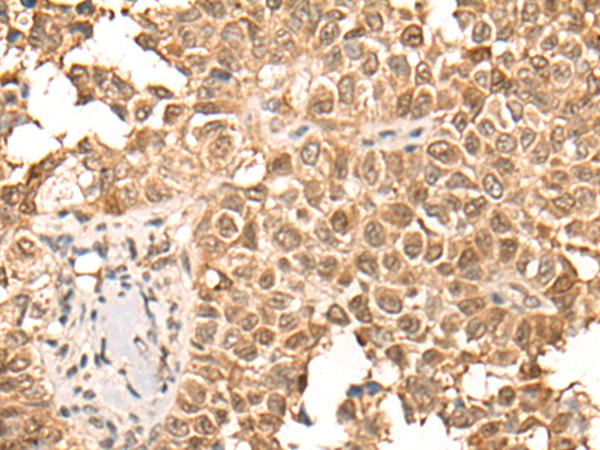

IHC positive control: |

Human ovarian cancer and human thyroid cancer |